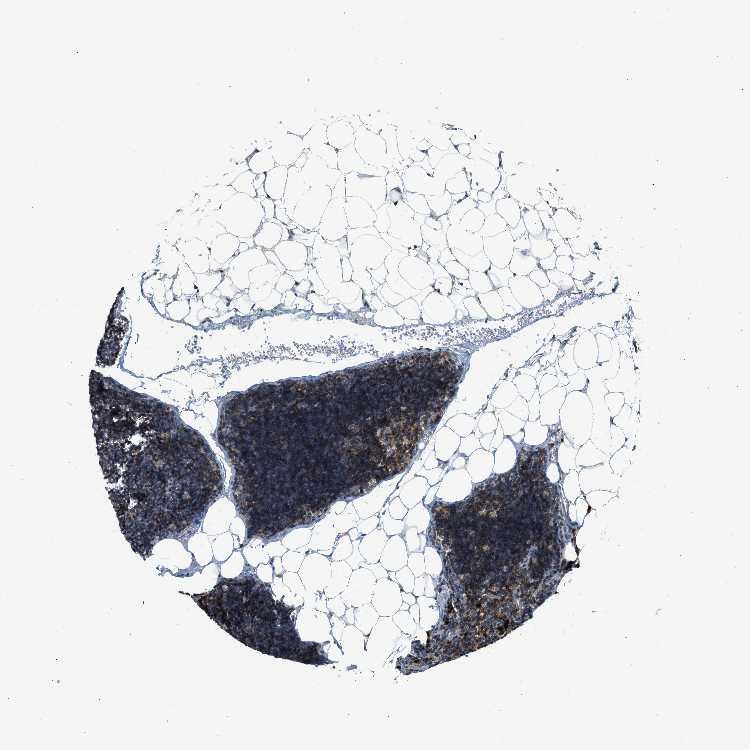

TISSUE PRIMARY DATA LYMPH NODE Show tissue menu

Lymph node

LYMPH NODE - Antibody stainingi

Antibody staining in the annotated cell types in the current human tissue is reported as not detected, low, medium, or high, based on conventional immunohistochemistry profiling in selected tissues. This score is based on the combination of the staining intensity and fraction of stained cells.

Each image is clickable and will lead to virtual microscopy that enables deeper exploration of all samples and also displays staining intensity scores, fraction scores and subcellular localization as well as patient and tissue information for each sample.

Antibody HPA014657

Germinal center cells Medium

Non-germinal center cells High